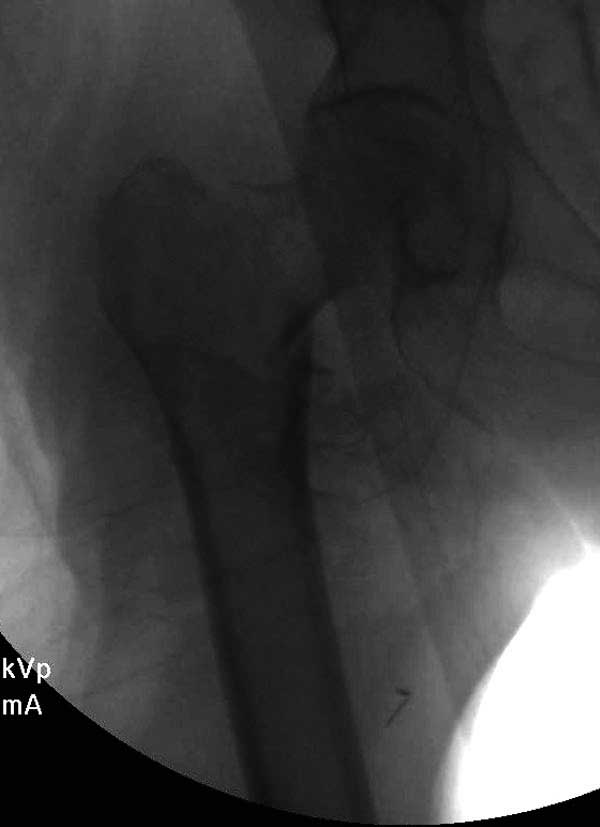

Первые снимки показывают технические погрешности установки DHS. Не была достигнута репозиция, конечность в флексии и шейка в ротации. Сегодня все меньше обращают внимание на параметры для оценки репозиции (S контуры Lowell в обеих проекциях и Garden Alignment Index, в норме 155 и 180 градусов), хотя такие простые тесты помогли бы дорепонировать смещение. Винт находится сзади в головке, что при нагрузке поменяет вектор и вместо компрессии в линии перелома срежет головку-Cut Out!

В зависимости от дистанции линии перелома и латерального кортекса надо использовать разной длины barrel, т.е. конец баррели не должен доходить до пределов перелома. Здесь конец длинного ствола упирается в медиальный фрагмент, что мешает созданию компрессии, а более короткий barrel создал бы запас для компрессии. В боковой пластине вместо 4х можно было ограничится двумя шурупами, потому что головка шурупа в 4.5 мм выдерживает давление до 350 кг.